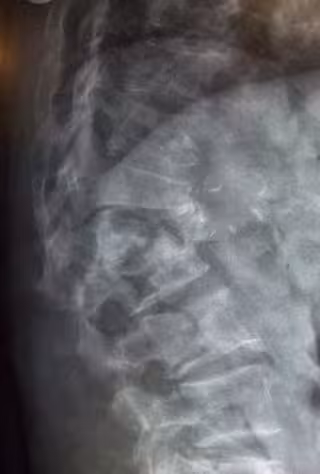

osteoporosis

WIKIMEDIA COMMONS